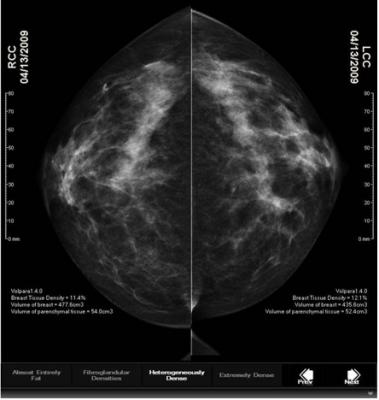

April 29, 2015 — Volpara Solutions announced the release of VolparaDensity version 3.1 at the Society of Breast Imaging’s SBI/ACR Breast Imaging Symposium in Orlando, Florida, April 25-28.

The latest version of VolparaDensity supports digital mammography from all leading vendors and tomosynthesis datasets from Hologic, GE and Siemens tomosynthesis systems. Additionally, VolparaDensity 3.1 supports Hologic sites that use C-View synthetic 2-D images and GE SenoClaire sites that acquire 2-D CC and 3-D MLO images. VolparaDensity uses the same algorithm to process both the acquired tomosynthesis projections and the raw data of a conventional 2-D mammogram. This reduces the challenges of visually determining breast density based on a review of tomosynthesis slices and the new synthetic 2-D images (C-View from Hologic, V-Preview from GE).

“We have been using VolparaDensity for more than two years and find it particularly helpful when assessing breast density in mammograms with a complex dispersion of fibroglandular tissue,” said Kathy Schilling, M.D., of the Christine Lynn Women's Health and Wellness Center at Boca Raton Regional Hospital in Boca Raton, Florida. “We are now very pleased to be using VolparaDensity together with our GE SenoClaire digital breast tomosynthesis acquisitions. Given the demands of reviewing the stacks of tomosynthesis slices and the new synthetic 2-D images, we appreciate the consistent density assessment we get from the Volpara software.”

VolparaDensity 3.1 supports additional features including new configuration flexibility for patient-specific compression pressure calculations and the ability to route patient results by Volpara’s U.S. Food and Drug Administration (FDA)-cleared Volpara Density Grades (VDG), which are analogous to the BI-RADS density categories. Based on a site’s imaging protocols for breast density and risk, users can configure the system to automatically send density results for women with very dense breasts to a specific interpreting radiologist or a breast density specialist at the site for review. This automatic routing may help improve the speed with which sites can identify women who would benefit from additional screening, particularly sites that perform same-day adjunctive screening.

VolparaDensity is in use at breast imaging centers worldwide to help radiologists objectively assess density from both digital mammography and tomosynthesis images and to determine which women would benefit from additional screening. Highly correlated to breast magnetic resonance (MR) assessments, VolparaDensity automatically generates an objective measurement of volumetric breast density correlated to the American College of Radiology (ACR) breast density categories.